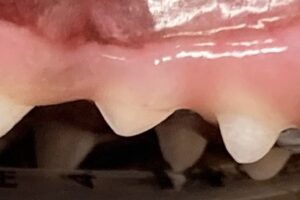

犬や猫の口は、(食後を除いて)無臭であることが本来の状態とされています